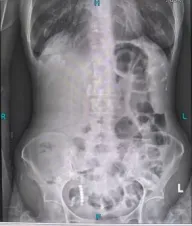

林奶奶的身体早已被病痛反复透支:4年前,她因子宫平滑肌肉瘤接受了一场大手术,术后虚弱不堪,无法承受后续化疗,只能靠定期复查勉强维持。原以为能平稳度日,没想到1个月前,无明显诱因的全腹胀痛突然袭来。随着时间推移,疼痛越来越剧烈,还伴着恶心、无法进食,最终完全停止排气排便。这让本就虚弱的林奶奶焦虑不已,担心自己扛不住新一轮手术治疗。

根据林奶奶的情况,团队最终确定林奶奶的“救命招”——病房床旁胃镜下肠梗阻导管置入术,这也是针对重症梗阻患者的特色技术。考虑到林奶奶疼痛难忍、无法移动,叶晋生团队在床旁不到10分钟便完成了肠梗阻导管植入术,随着大量的肠液被引出,林奶奶的腹胀腹痛症状得到了有效缓解。

这根长达280cm的特殊导管,比普通胃管更长、更精准,能借助胃肠蠕动直达梗阻部位,实现充分减压——不仅快速缓解了肠梗阻带来的腹胀腹痛,为后续手术创造安全条件。与此同时,团队同步给予静脉肠外营养支持,确保林奶奶在术前维持良好的营养状态,为手术耐受打下基础。

导管置入后,林奶奶的症状明显缓解,叶晋生通过进一步检查发现,林奶奶的肠梗阻并非单纯粘连所致,而是盆腔占位压迫肠道,考虑为子宫平滑肌肉瘤复发,且已侵犯直肠及膀胱,必须通过手术切除病灶才能从根源解决问题。叶晋生第一时间启动多学科会诊,麻醉科、ICU、消化科、肿瘤科等科室专家,共同评估病情及围手术期风险,